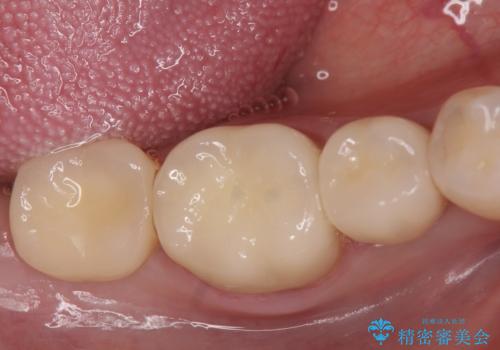

オールセラミッククラウンについて

今回用いたオールセラミッククラウンはジルコニアフレームという白い素材の上にセラミックを盛っているため、審美性が非常に高いのが特徴です。

また、ジルコニアは人工ダイヤモンドの材料にも使われているほど高い強度を持っており、そのためオールセラミッククラウンは審美性だけでなく、奥歯やブリッジの補綴も可能とするクラウンです。